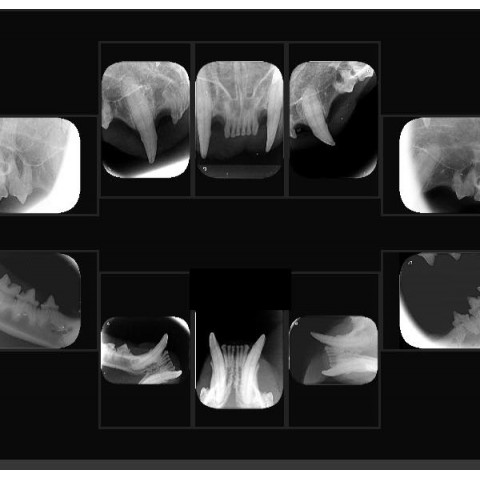

專業獸醫師都知道:「No dental X-ray, no dentistry!」

「No dental X-ray, no dentistry!」沒有X光,就不要隨便動牙齒! 前一陣子聽到家長稱讚我們的牙科做得很仔細,多了很多毛孩沒做過的牙科流程,還拍了以前洗牙從沒拍過的牙科X光。 雖然聽到稱讚還是會小小暗爽一下,但還是得跟...